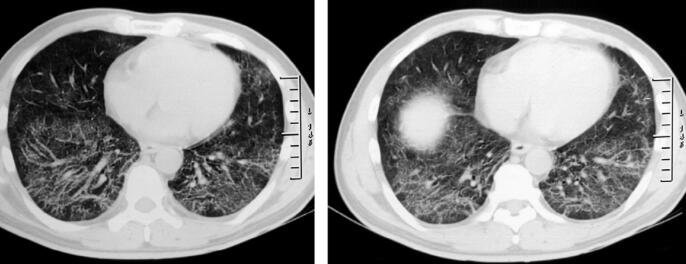

经莫西沙星治疗3天后体温稍降低,但仍可达38℃。双肺干鸣音较前增加,呼吸困难无缓解。此间实验检查结果:①血常规复查:白细胞计数7.16×109/L;中性粒细胞百分比67.9%;淋巴细胞百分比25.0%;②胸部X线检查(治疗一周后):双肺磨玻璃样影改变较前增多(图2);③无黑便,便常规:便隐血(+)。

图2

患者拟诊为CAP,经过治疗病情好转不明显,应该考虑两个问题:①是否为特殊病原体感染?②是否为非感染性疾病?根据患者的临床特点及胸部影像学为双肺广泛磨玻璃样影,应注意排除可能形成磨玻璃样影的疾病如病毒感染、过敏反应、风湿免疫性疾病肺累及、ANCA相关性血管炎等。患者黑便,应除外消化系统疾病:消化性溃疡、溃疡性结肠炎、肠结核、克罗恩病、消化系统肿瘤等,建议完善钡餐、胃镜及肠镜等相关检查,患者拒绝。因此,重新深入询问病史,并进行有针对性的检查非常重要。